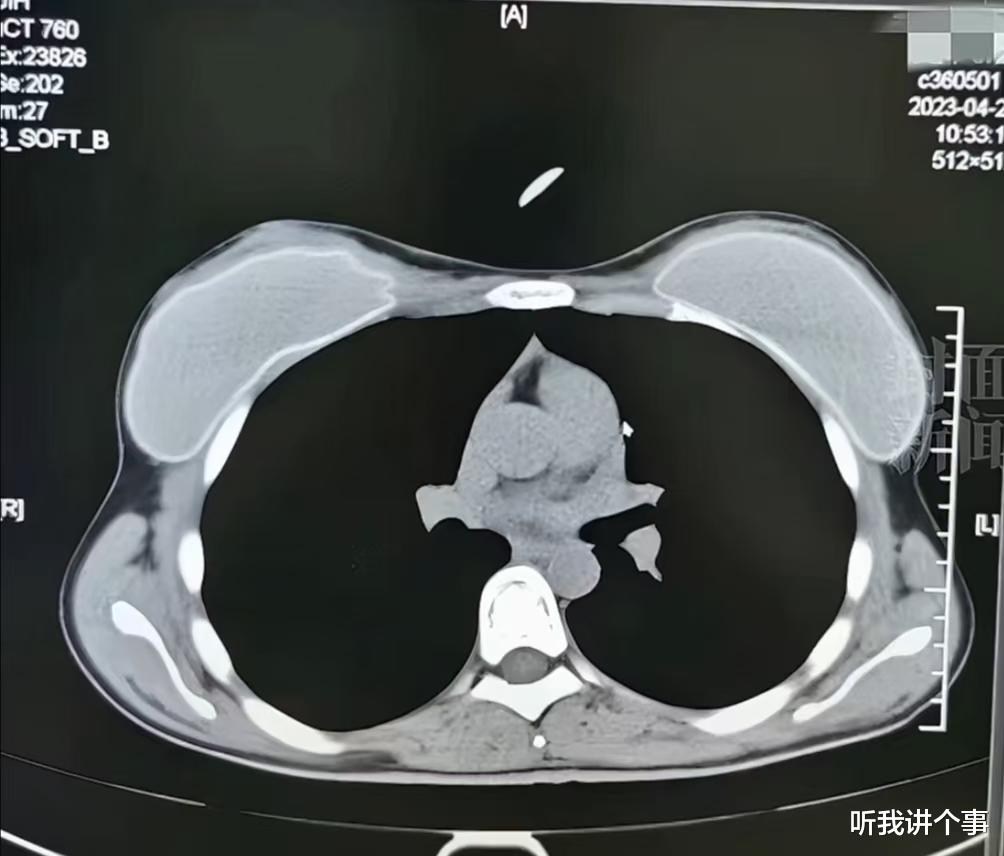

首先,让我们来捋一捋这个事件的来龙去脉。无锡虹桥医院的放射影像科医生朱成罡,实名举报自家医院存在骗取医保的行为。这可不是小打小闹,举报的内容让人瞠目结舌:26岁、62岁、72岁患者的CT片竟然长得“一模一样”,这不是明摆着的造假吗?

这些“子虚乌有”的CT片,每张价值300到600元,而且都是医保买单。这不是明摆着的“空手套白狼”吗?朱医生一举报,事情就更加扑朔迷离了。放射影像科的医生们突然就失去了查看2023年8月之前影像的权限,院方给出的理由是“系统升级”。这不禁让人想问,这系统升级是升级了个寂寞吗?